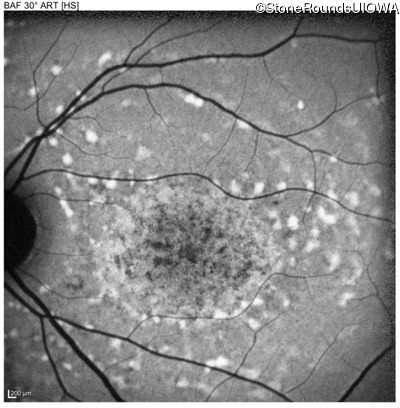

Age at visit: 22 years

OD OS

Age at visit: 17 years

Age at visit: 18 years

Age at visit: 19 years